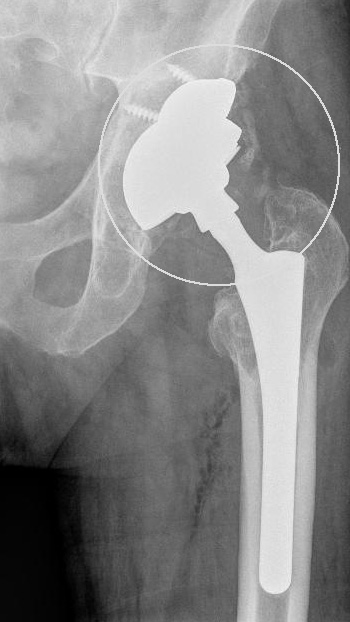

Bei der Prothesenplanung ist es für ein dauerhaft gutes Ergebnis entscheidend, die Pfannengröße und Schaftlänge optimal auf die anatomischen Gegebenheiten des Patienten anzupassen. Das Röntgenbild der Hüftprothese zeigt ein mechanisches Problem, das zu einer frühen Lockerung geführt hat: Die Schaftlänge wurde hier nicht optimal gewählt und der Zementmantel um die Prothese ist nicht ganz gleichmäßig. Der Oberschenkelknochen zeigt in der Höhe des Trochanters, einem seitlichen Knochenvorsprung des Oberschenkelknochens (Markierung 1), eine deutlich verminderte Knochendichte. Die Tragfähigkeit des Femurs (Oberschenkelknochen) ist also bereits vermindert. Der zementierte Prothesenschaft hat sich aufgrund der ungünstigen Geometrie gelockert und ist im Markraum des Oberschenkels verkippt. Eine schmerzhafte Sinterung (Einsinken der Prothese in den Oberschenkel) mit Beinlängenverkürzung ist die Folge. Der Patient konnte ohne Gehhilfe nicht mehr gehen. Seine maximale Gehstrecke war infolge der gelockerten Hüftprothese stark eingeschränkt.

Für die Wechseloperation wurde eine Prothese mit einem einwachsendem Langschaft, der tief im Oberschenkelknochen verankert ist, gewählt. Dies entlastet den geschwächten Trochanter (seitlicher Knochenvorsprung des Oberschenkelknochens). Tiefere Anteile des Oberschenkels beteiligen sich an der Last. Keramischer Ersatzknochen verstärkt die Knochenbildung am Trochanter, damit sich die Knochensubstanz in diesem Bereich wieder regeneriert. Der Patient war nach der Wechseloperation wieder beschwerdefrei.